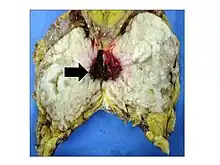

Phyllodes tumors may be considered benign, borderline, or malignant depending upon their histological features, including stromal cellularity, infiltration of the epithelial-stromal interface, and mitotic activity.[15] Due to their propensity to metastasize and grow quickly, almost all phyllodes tumors are regarded as having malignant potential and treated accordingly.[15] A large case series from the MD Anderson Cancer Center reported the incidence of each type of phyllodes tumor as benign (58%), borderline (12%), and malignant (30%).[16]

Malignant phyllodes tumors can behave similarly to sarcomas leading to development of blood-borne metastases.[16] Approximately 10% of phyllodes tumor develop distant metastases and this occurrence is higher (20%) in patients with histological-identified malignant tumors.[16] The most common site for distant metastases include the lung, bone, and abdominal viscera.[17] In more insidious cases, the parotid region has also been described in literature.[18]